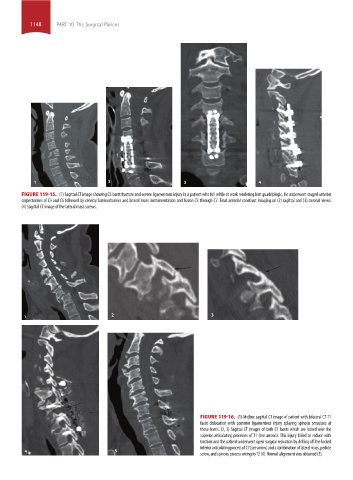

FIGURE 119-15. (1) Sagittal CT image showing C5 burst fracture and severe ligamentous injury in a patient who fell while at work rendering him quadriplegic. He underwent staged anterior

corpectomies of C5 and C6 followed by cervical laminectomies and lateral mass instrumentation and fusion C3 through C7. Final anterior construct imaging on (2) sagittal and (3) coronal views.

(4) Sagittal CT image of the lateral mass screws.

FIGURE 119-16. (1) Midline sagittal CT image of patient with bilateral C7-T1

facet dislocation with posterior ligamentous injury splaying spinous processes at

these levels. (2, 3) Sagittal CT images of both C7 facets which are locked over the

superior articulating processes of T1 (see arrows). This injury failed to reduce with

traction and the patient underwent open surgical reduction by drilling off the locked

inferior articulating process of C7 (see arrow) and a combination of lateral mass, pedicle

4 5

screw, and spinous process wiring to T2 (4). Normal alignment was obtained (5).